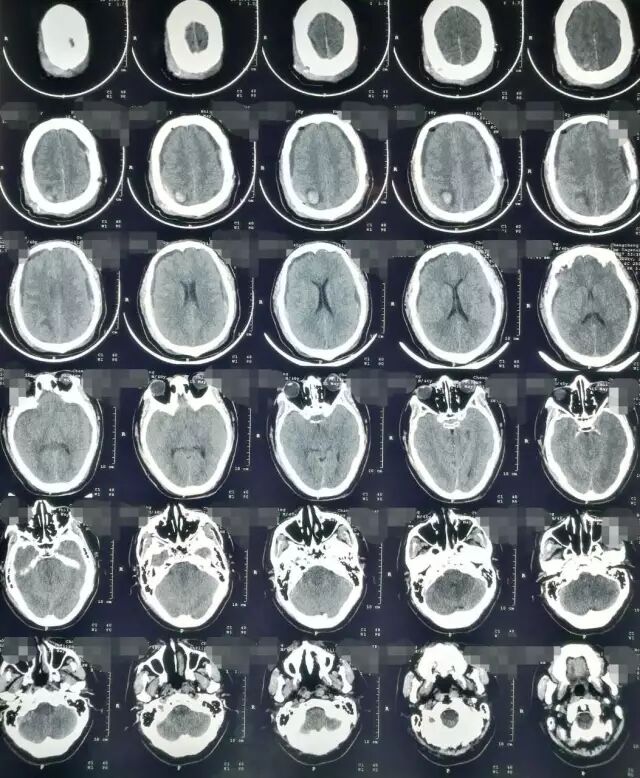

2017年5月7日上海某医院头颅CT提示:颅脑术后,双侧额颞顶部硬膜下积液积血(图4)。于2017年5月9日行双侧钻孔引流术,2017年5月12日头颅CT提示:钻孔术后改变,颅内积气(图5)。患者术后头痛症状持续加重,出现意识不清,5月15日再次复查头颅CT提示脑肿胀明显(图6),于5月17日再次行右侧硬膜下血肿清除+左侧硬膜下血肿钻孔引流术,术后患者出现脑疝,于2017年5月21日行右侧额颞顶扩大去骨瓣减压术+血肿清除术。(图7)

图4. 5月7日头颅CT提示双侧硬膜下积血积液。

图5. 2017年5月12日复查头颅CT提示:钻孔术后改变,颅内积气。

图6. 2017年5月15日头颅CT显示脑沟脑池不清晰,脑肿胀明显。

图7. 2017年5月22日外院头颅CT提示:右侧额颞顶部去骨瓣术后改变。

图8. 2017年7月4日本院头颅CT提示:右侧额颞顶部去骨瓣术后改变,脑室扩张。